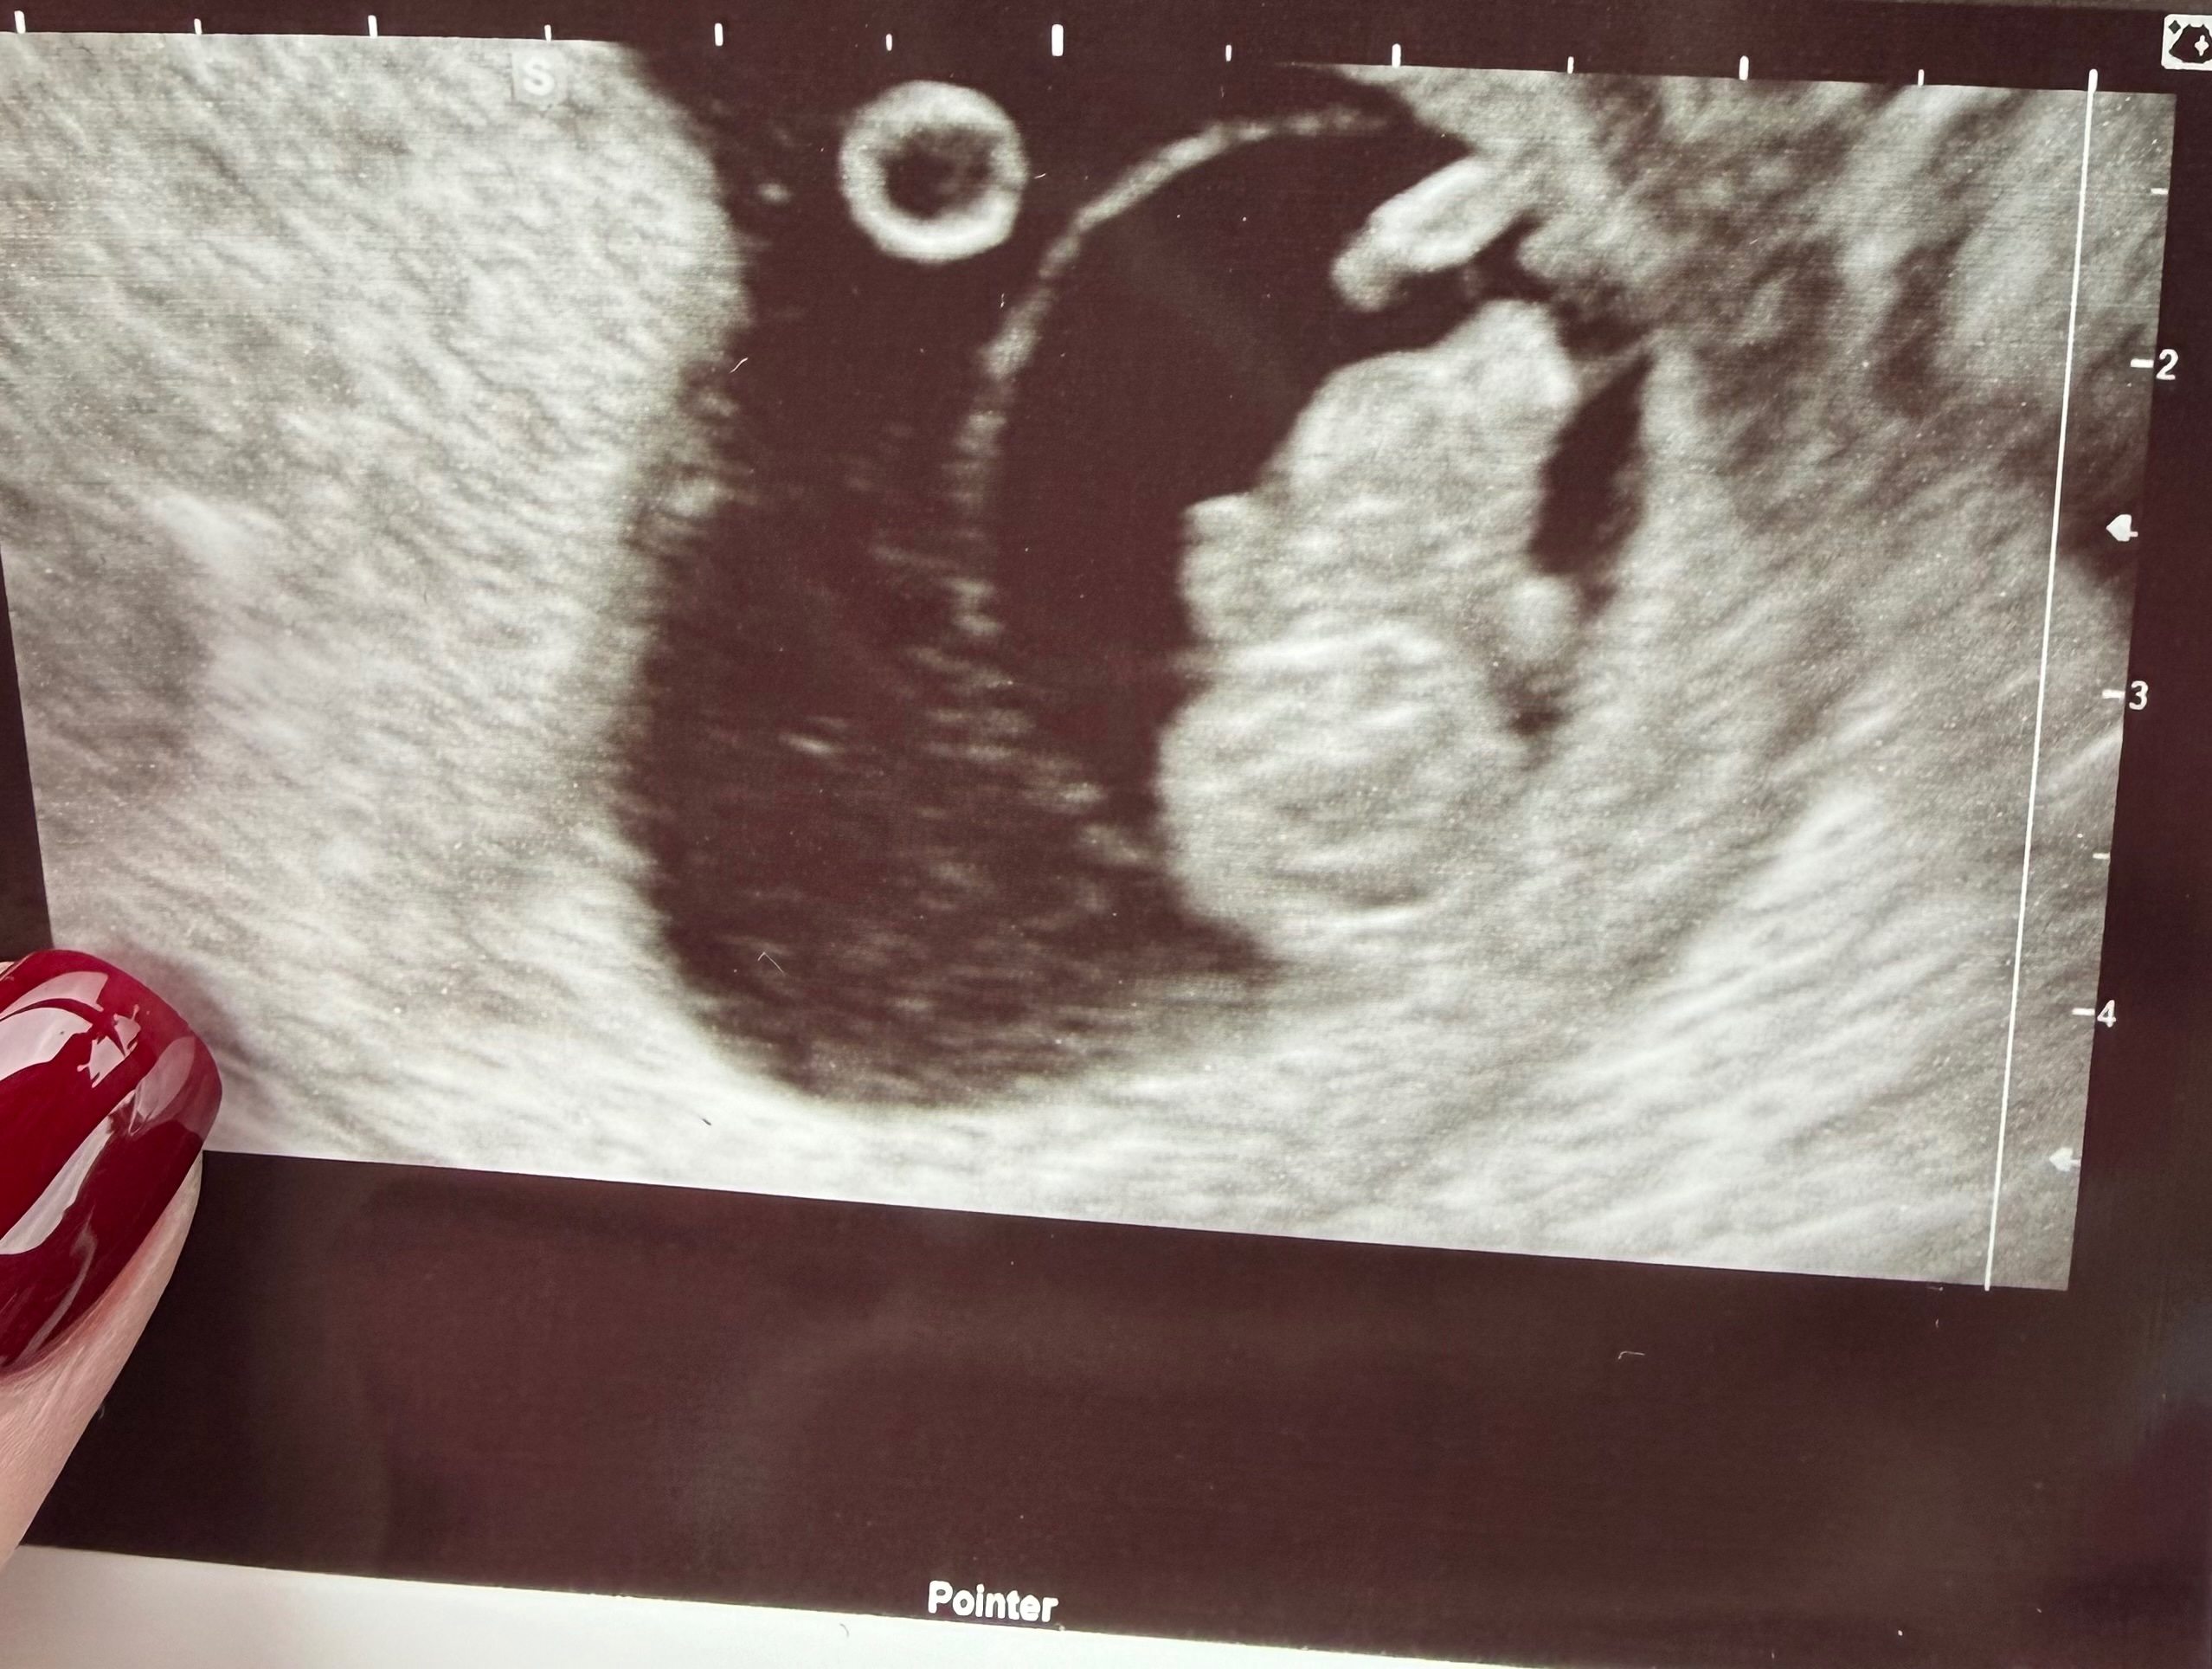

U nas mały człowieczek ma 2,6cm❤️❤️❤️

Serduszko 169ud/min.

Zdjęcie słabe i ogólnie bardziej trzeba się domyślić co jest gdzie, ale na żywo pomachał mi maluszek ręką🥹🥹🥹

Niestety lekarz nie zgodził się na nagrywanie więc muszę zatrzymać obraz tego ruchu w pamięci🤷‍♀️

Najważniejsze, że wszystko na chwilę obecną jest tak jak powinno być! Zdjęcia są miłym dodatkiem, ale są mniej ważne niż dane i informacje od lekarza. 🎉

• Screenshot_20260409_163536_Gallery.jpg

Screenshot_20260409_163536_Gallery.jpg

84,1 KB · Wyświetleń: 26